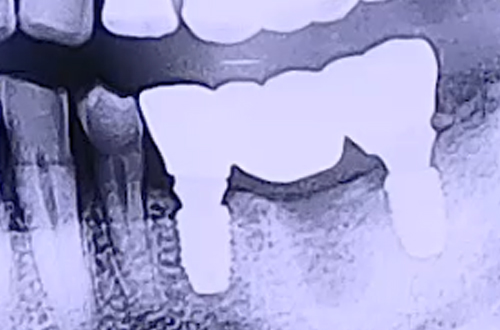

BEFORE

검사를 해본 결과 왼쪽 아래 어금니에 진행한 임플란트 앞의 어금니 하나가 머리가 깨져 뿌리만 남아있었고, 해당 부분에 식립된 임플란트 2개는 임플란트 주위염이 진행된 상태로 잇몸이 많이 붓고 약해져 있었습니다.

임플란트 주위염 발생의 이유는 해당 임플란트가 똑바르지 않고 기울여 심어진 탓으로 보였는데요. 임플란트를 심을 때는 주변 치아들과 같이 똑바로 심어야 한다는 원칙이 지켜지지 않은 것입니다.

이렇게 비뚤게 식립된 임플란트는 환자분들께서 열심히 관리를 해 주어도 그 사이에 생긴 틈새 등의 이유로 원활하게 관리가 이루어지기 어려워 주위염을 불러올 수 있죠. 따라서 기존 임플란트와 그 앞에 남아있는 치아 뿌리를 제거하고 재수술을 진행하였습니다.